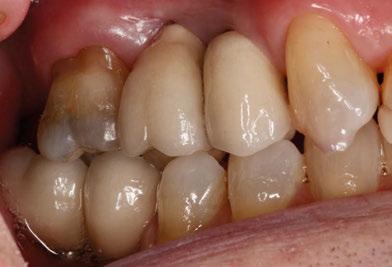

A partir del estudio radiológico y de las imágenes fotográficas podemos observar edentulismo de 17, 15, 14, 12,

25, 26, 28, 37, 38, 47 y 48. Presentaba corona desajustada en 13 con extensión en 12, implantes en 35-36, 45-46, con coronas ferulizadas en 35-36, 45-46, y dientes anteriores superiores con enfermedad periodontal Grado IV.

El paciente presentaba biotipo periodontal grueso, con márgenes asimétricos, con recesiones gingivales a nivel de 11 y 13 y pérdida de tejidos blandos interproximales.

3. Exploración de tejidos duros

En la exploración radiográfica (OPG, CBCT) observamos la existencia de pérdida ósea interproximal, lesión apical a nivel de la raíz mesial del 27 y el cordal del primer cuadrante incluido y neumatización sinusal del primer y segundo cuadrante.